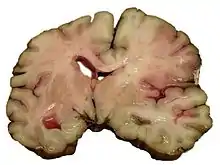

Intracerebral hemorrhage

It generally occurs in small arteries or arterioles and is commonly due to hypertension,[49] intracranial vascular malformations (including cavernous angiomas or arteriovenous malformations), cerebral amyloid angiopathy, or infarcts into which secondary hemorrhage has occurred.[2] Other potential causes are trauma, bleeding disorders, amyloid angiopathy, illicit drug use (e.g., amphetamines or cocaine). The hematoma enlarges until pressure from surrounding tissue limits its growth, or until it decompresses by emptying into the ventricular system, CSF or the pial surface. A third of intracerebral bleed is into the brain's ventricles. ICH has a mortality rate of 44 percent after 30 days, higher than ischemic stroke or subarachnoid hemorrhage (which technically may also be classified as a type of stroke[2]).